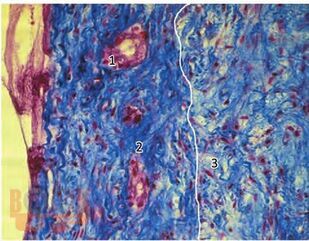

В монографии представлены результаты многолетнего опыта работы по изучению этиологии, патогенеза и исходов одонтогенных верхнечелюстных синуситов в повседневной практике врачей-оториноларингологов и стоматологов. Представлены уникальные данные о причинах и условиях возникновения синуситов, механизмах развития, течения и исходах, а также результатов морфологических исследований в зависимости от характера этиологических факторов и факторов риска. Представлены инновационные методы диагностики и лечения синуситов, обеспечивающие персонализированный подход в прогнозировании исхода заболевания.